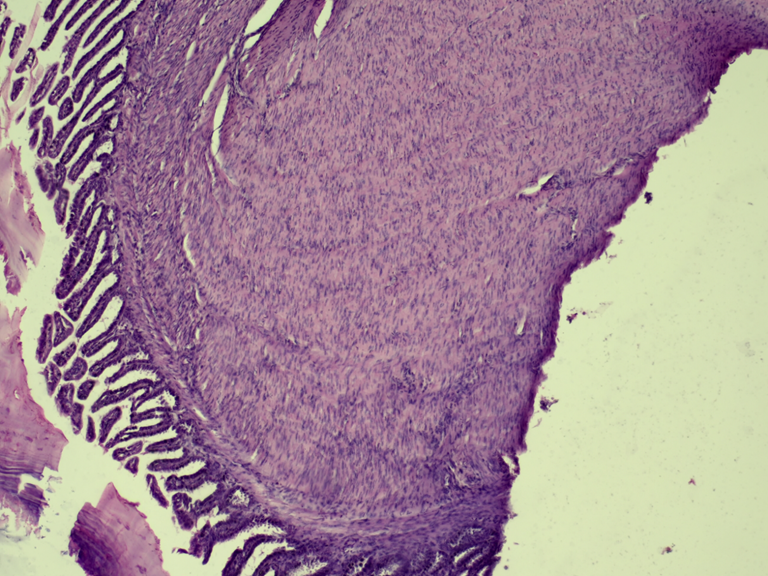

The radiographic study did not refer conclusive results. Post-mortem evaluation revealed small intestine with marked wall thickening. In serial sections of the small intestine stained with hematoxylin-eosin (HyE), a thickened longitudinal muscular tunic was evaluated, with palisade proliferation, slightly disorganized, of parallel spindle cells with a central nucleus and homogeneous eosinophilic cytoplasm (Fig. 1 y 2). Lamina propria and submucosa with marked congestion in blood vessels. No mitotic figures or cellular atypia were observed. Histopathological diagnosis referred intestinal leiomyoma.

Figure 1: Small Intestine. Muscular tunic with dense, non-encapsulated erosion of smooth muscle fibers. Mucosa without histological alterations. H-E. 20x